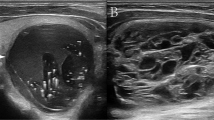

A physician more than 5-year experiences in ultrasound diagnosis marked the anteroposterior diameter and transverse diameter of the original standard images of 296 thyroid nodules with the cursor. Patient data and characteristics were blinded in AmCAD-UT application. Then the computer automatically traced the initial contour of ROI, identified the ultrasound image features of the thyroid nodules, then labeled and quantified the features in different colors, including echo type of the nodules, solid/cystic nature, uniformity of echo, nodular morphology, aspect ratio, and with or without microcalcification (Figs. 1, 2). Finally, the CAD system automatically generated the malignancy risk assessment report and suggestions of thyroid nodules based on 2015 ATA Guidelines [5], 2017 ACR TI-RADS Guidelines [8], 2016 AACE/ACE/AME Guidelines [18] and 2011 Kwak TI-RADS Guidelines [19] in the program.